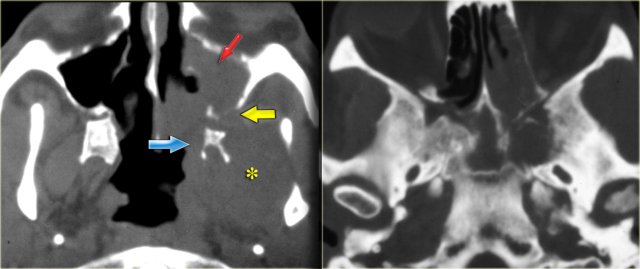

On the left CT-images of a patient post-lung transplant with fever and multiple rapidly progressing cranial nerve palsies.

We will show you CT- and MR-images of this patient. The diagnosis lymphoma was made through biopsy.

First study the images to study the extention od the disease.

Then continue reading.

Lymphoma of sphenoid sinus and skull base Lymphoma of sphenoid sinus and skull base

On the CT-images the findings are:

• Soft tissue mass in the maxillary sinus (red arrow).

• Destruction of the sinus wall (yellow arrow).

• Remodelling and destruction of the pterygoid bone (blue arrow).

• Large soft tissue mass in the masticator space (asterisk).

The image on the right is more cranial.

There is opacification of the sphenoid sinus with destruction of and osteopenia of the sphenoid bone.

CT nicely demonstrates the bone destruction and some of the soft tissue involvement.

Continue with the MR-images.